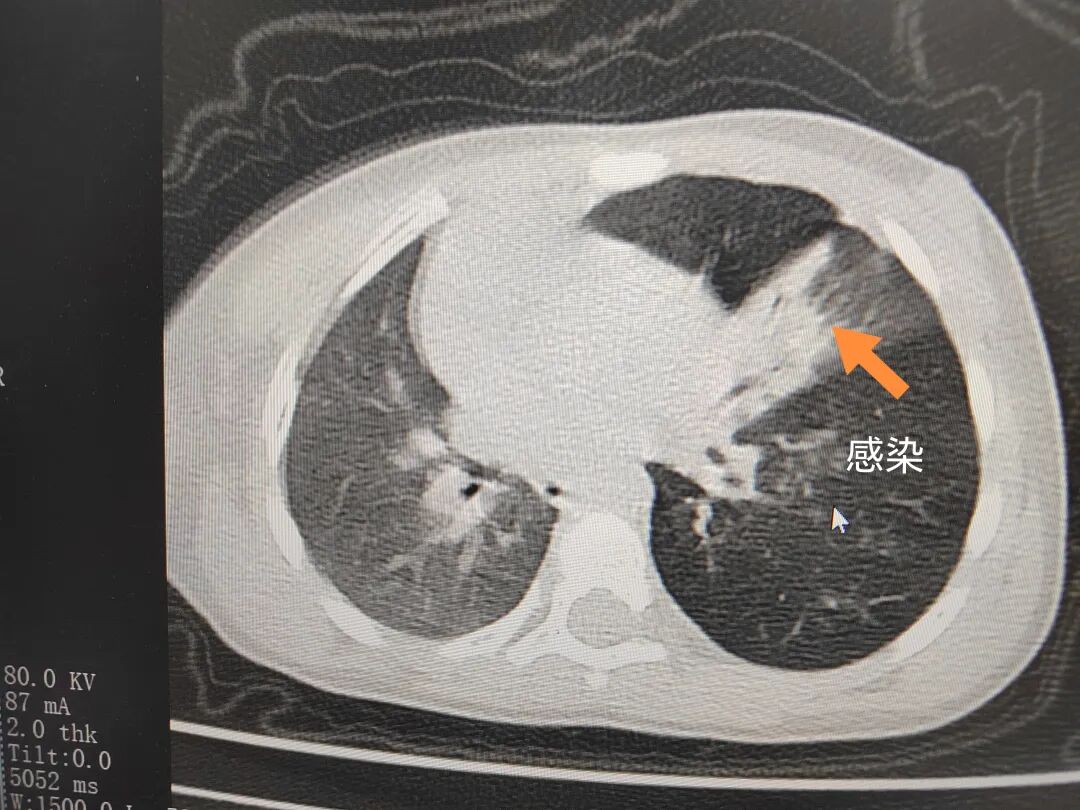

三天后(11月13日),趙寶出現(xiàn)高熱、咳喘加重,家長(zhǎng)著急了,再次帶他來(lái)到醫(yī)院。CT檢查顯示左肺過度充氣,左肺上下葉支氣管主干見不規(guī)則高密度影,左肺上葉可見大片狀密度增高影,縱隔窗實(shí)變,提示為“左側(cè)支氣管內(nèi)異物并繼發(fā)性改變,左肺上葉舌段肺膨脹不全”。

市二院小兒呼吸內(nèi)科團(tuán)隊(duì)迅速為患兒制定了周密的手術(shù)方案,并很快安排了氣管鏡探查。術(shù)中,主治醫(yī)師田慧等憑借嫻熟的氣管鏡操作技術(shù)成功將異物大塊板栗取出。由于板栗在氣管內(nèi)存留時(shí)間較長(zhǎng),質(zhì)地軟糯易碎,大大增加了手術(shù)難度。檢查還發(fā)現(xiàn),異物停留部位的氣管黏膜已出現(xiàn)充血紅腫、糜爛,導(dǎo)致患兒住院時(shí)間相應(yīng)延長(zhǎng)。此次事件給趙寶的家庭帶來(lái)了不小的驚嚇與擔(dān)憂,也再次為廣大家長(zhǎng)敲響了警鐘。

市二院小兒呼吸內(nèi)科副主任楊亞娟介紹,異物誤入氣道可能導(dǎo)致氣道阻塞,嚴(yán)重時(shí)可引發(fā)窒息,甚至危及生命。若異物進(jìn)入支氣管,造成不完全堵塞,可引起阻塞性肺氣腫;如完全堵塞支氣管,則可能導(dǎo)致肺組織萎縮,形成肺不張。此外,若異物存留時(shí)間較長(zhǎng),或?yàn)橹参镄援愇?,容易合并?xì)菌感染,產(chǎn)生膿性分泌物,進(jìn)而發(fā)展為肺炎。她強(qiáng)調(diào),盡早診斷并取出異物,是減少并發(fā)癥、降低病死率的關(guān)鍵。